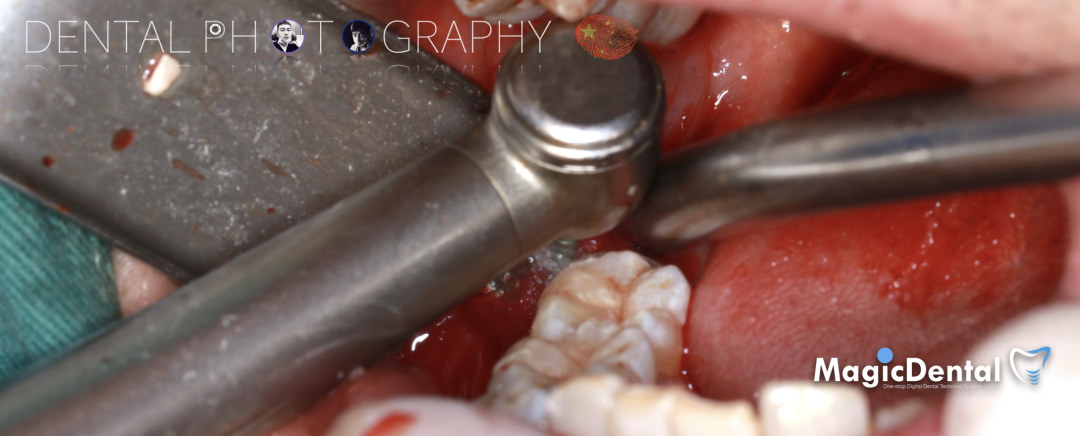

切开翻瓣,彻底暴露术区,试戴骨块。

调整骨块外形,适配受植区域,打开骨髓腔。

预备固位钉洞,固定骨块

骨膜减张,放置骨粉,放置骨块,钛钉固定骨块。

固定骨片,修整骨块边缘,继续放置骨粉覆盖骨块及受植区,放置骨膜,严密缝合创口。